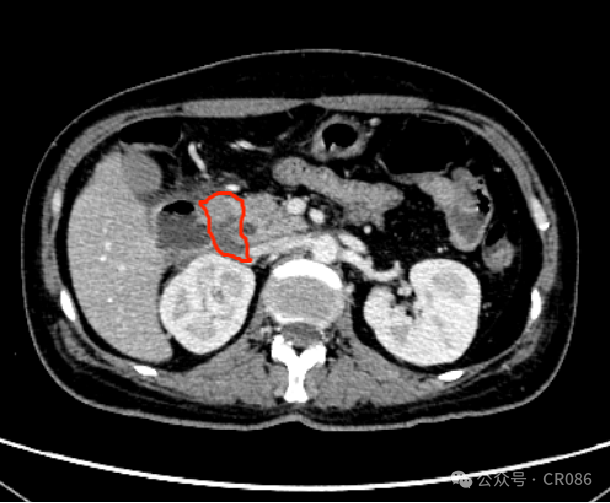

11月底,移植科医生发了一张CT影像报告给我,说:“洪飞,你还记的这个病人么?肿瘤已经快没了!”我对照了一下病情,不敢相信自己的眼睛。是的,袁姐之前半个腹腔的巨大肿瘤,在CT上已经只有一点点残留影子了。

4.png

2024年11月25日 2轮维奈克拉联合方案后

我问医生,怎么做到的?“很简单,我们用了维奈克拉联合的化疗方案”。他轻描淡写的得瑟着自己的成果。